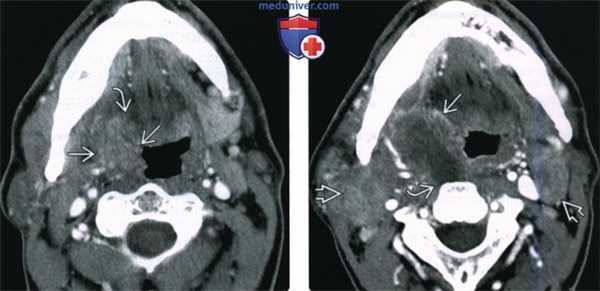

(Слева) При аксиальной КТ с КУ в левой половине шеи визуализируется большое однокамерное кистозное образование, имитирующее кисту второй жаберной щели по своему расположению. Обратите внимание на объемное образование в области нижнего полюса левой небной миндалины.

(Справа) При аксиальной КТ с КУ на более каудальном уровне визуализируется кистозно-некротическое объемное образование, расположенное снаружи от сонного влагалища, сзади от поднижнечелюстной слюнной железы спереди и изнутри от грудино-ключично-сосцевидной мышцы. Объемное образование напоминает кисту второй жаберной щели, но представляет собой метастаз ВПЧ(+) ПКР миндалины в лимфоузел.

2. КТ при ВПЧ-обусловленном плоскоклеточном раке ротоглотки:

• КТ с контрастным усилением:

о Лимфаденопатия варьирует: от единственного солидного или кистозного лимфоузла до массивной многоуровневой лимфаденопатии

- Обычно лимфоузлы II и III уровня; могут быть явно кистозными

- Неровные края лимфоузла и «грязная» жировая клетчатка свидетельствует об экстракапсулярном распространении (ЭКР):

Согласно данным патологов, периодическое воспаление тканей рядом с лифоузлом может имитировать ЭКР

о Объемное образование различного размера в миндаликовой ямке или в корне языка, накапливающее контраст:

- Первичная опухоль ротоглотки: различные размеры и стадии, в т.ч. «немая» опухоль

- Распространение опухоли в наружные мышцы языка или в полость рта, в надсвязочный отдел гортани, медиальную крыловидную мышцу, твердое небо, нижнюю челюсть повышает стадию до Т4а